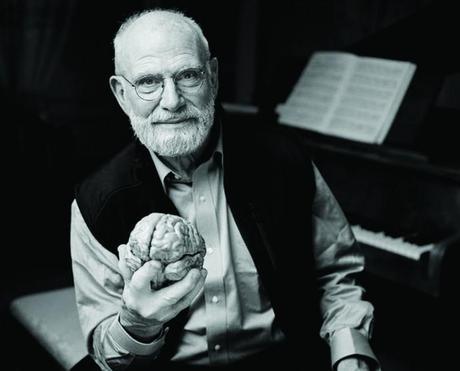

“Hace un mes, pensaba que tenía buena salud, incluso que estaba fuerte. A los 81 años, aún nado una milla cada día. Pero mi suerte se ha acabado: hace unas semanas descubrí que tengo una metástasis múltiple en el hígado”. Así empieza la elocuente carta de Oliver Sacks en The New York Times en la que hace público que sólo le quedan unos meses de vida y que piensa aprovecharlos al máximo.

Sacks es un neurólogos más reconocidos del mundo, autor de bestsellers traducidos en 25 idiomas como: El hombre que confundió a su mujer con un sombrero y Despertares, libros que nos permitieron conocer más de cerca algunos de los trastornos neurológicos menos comunes y no desde una descripción médica, sino desde las perspectivas de las personas que las viven.

Hace nueve años descubrió que tenía un raro tumor en el ojo, un melanoma ocular. Aunque el tratamiento que recibió lo dejó ciego en ese ojo, el tumor raramente metastatiza y él se encuentra en el 2% de las personas con mala suerte. Pero aún con este diagnóstico. Sacks no se siente acabado sino más bien quiere aprovechar cada minuto para vivir la vida lo más rica y productivamente posible.

¨Me siento agradecido de que se me han concedido nueve años de buena salud y de productividad. Pero ahora estoy cara a cara con la muerte. Ahora depende de mí cómo vivir los meses que me quedan. Tengo que vivir de la manera más rica, más profunda, más productiva que pueda.¨

Sacks ha escrito un ensayo conmovedor que nos enseña a aprovechar cada minuto y a demostrar gratitud por todo lo que hemos vivido. Te invito a que leas su escrito completo en el New york Times.